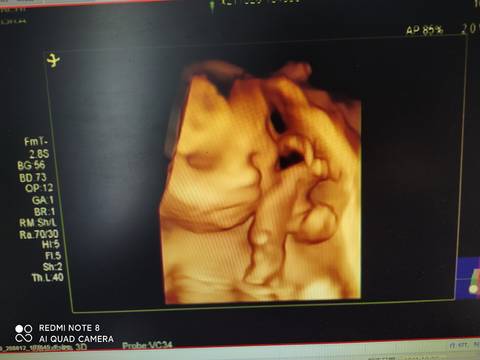

悬浮肚,太累人了,不知男孩女孩,医生只说宝宝大长腿

journal_insert_pic_1683086814journal_insert_pic_1683086854journal_insert_pic_1683086904